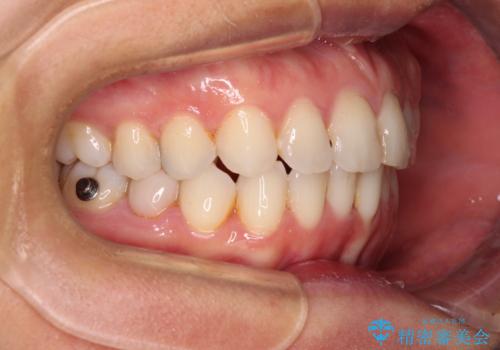

- 前歯のデコボコを気にして来院された患者様です。

IPR(歯と歯の間を削る)によってデコボコが解消するように設計し、インビザラインにより治療を行うこととしました。

下顎善の叢生をもう少し改善したかったのですが、患者様は十分に整ったとのことで治療を終えることになりました。